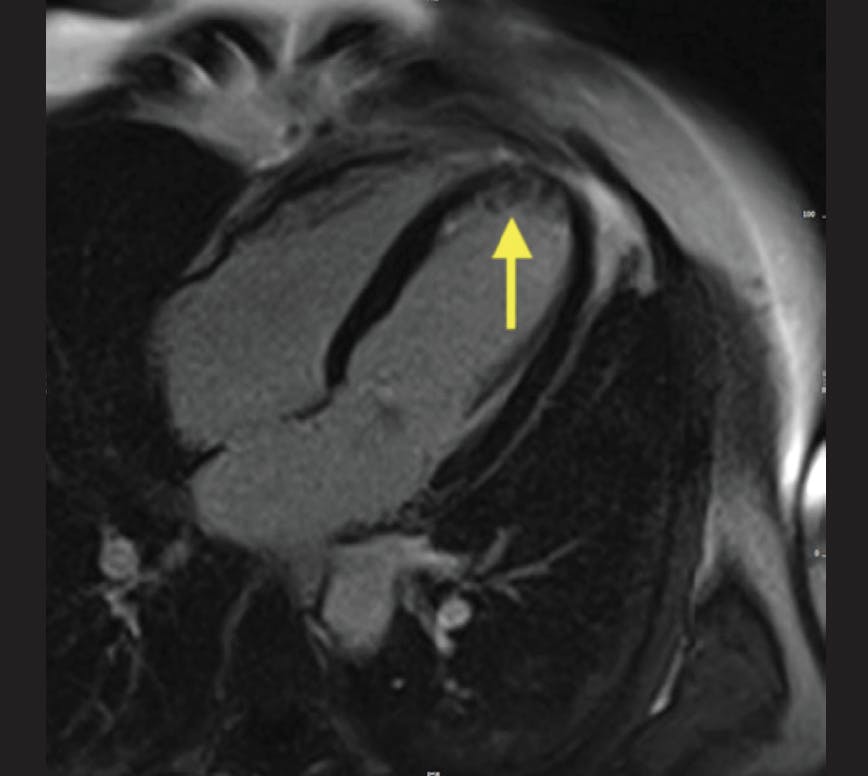

A woman in her mid 40s with no previous history of coronary artery disease, but low-density lipoprotein cholesterol (68 mg/dL) treated with atorvastatin and a 15 pack-year history of smoking, called the emergency medical team at 2:01 pm, 10 minutes after sudden onset of retrosternal chest pain radiating to the left arm. At 2:15 pm, a 12-lead electrocardiogram showed ST-segment elevations in anterior leads V2 to V5. Her blood pressure was 120/80 mm Hg and her heart rate was 95 beats per minute. The attending emergency physician in the ambulance administered 500 mg of acetylsalicylic acid, 5,000 IU of unfractionated heparin, and 10 mg of morphine via intravenous injection. The patient was handled according to the regional “STEMI Fast Track” and directly admitted to the cardiac catheterization laboratory at 2:55 pm. Focused transthoracic echocardiography revealed impaired LV function with anterior hypokinesia and an LVEF of 44%. The first angiogram, obtained at 3:05 pm, showed a proximally occluded left anterior descending artery that was successfully crossed with a guidewire at 3:28 pm (door-to-wire, 34 minutes) and three drug-eluting stents were implanted due to significant sequential coronary stenoses. SSO2 therapy was initiated by upgrading the femoral access to a 7-F sheath at 4:30 pm for withdrawal of arterial blood and positioning of a 5-F JL4 catheter within the ostium of the left main coronary artery for infusion of supersaturated blood. Intracoronary SSO2 therapy was applied for 60 minutes without incident. The patient was transferred to the chest-pain unit where a cardiac MRI performed on day 4 revealed that an extensive anteroapical region of the myocardium was at risk as indicated by edema (Figure 1). However, there was only a small region of nontransmural late gadolinium enhancement (Figure 2). The area at risk was calculated at 17 g (23.3% of the myocardium), with the final infarct size of 6.1 g (36% of the risk zone) resulting in a myocardial salvage index of 64%, with observation of 0% MVO. Based on a recent study by Park et al, we would have expected some MVO to be present in this case, and the salvage index in this case was higher than our expectations.13 The final LVEF was 60% by transthoracic echocardiography and 57% by MRI.

Figure 1. Area at risk as measured by MRI at day 4.